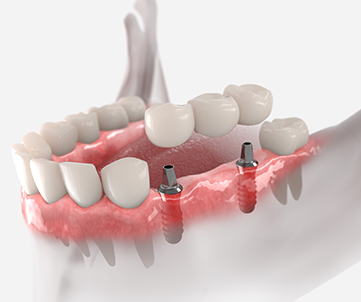

임플란트란 치아가 빠진 부위에 치아 뿌리와 동일한 형태의 인공치근을 식립하고 해당 부위에 인공치아를 결합하여 치아 기능을 대체하는 치료를 말합니다.

임플란트 치료과정